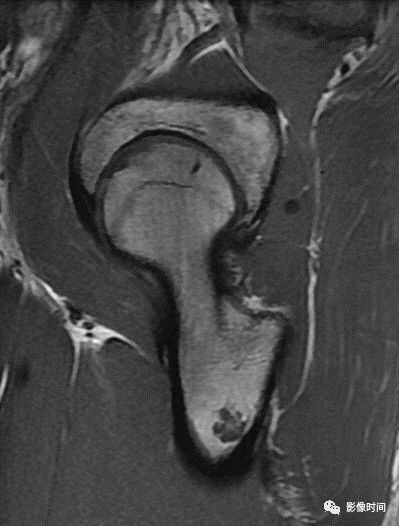

肿瘤对骨骺板和关节软骨的破坏是对骨破坏的继续。缺乏血管的骨骺板对恶性肿瘤有抵抗作用,骨骺板可暂时阻止肿瘤的蔓延,但当肿瘤进一步发展时, 骨骺板亦可被破坏,X 线平片或 CT 可表现为先期钙化带密度减低、中断或消失。MRI 可显示肿瘤从干骺端跨越骨骺板侵犯骨骺(图 15、图 16)。

肿瘤突破关节软骨向关节腔发展时, 可表现为关节面破坏、塌陷(图 17), 关节腔内出现软组织肿块。少数良性骨肿瘤如软骨母细胞瘤, 亦可超越骺板向两侧发展或突入关节腔内, 此为肿瘤膨胀生长所致, 而非浸润性破坏。

图 15  骨骺板破坏:骨肉瘤

图 16  骨骺板破坏:骨肉瘤

图 17  关节软骨破坏:骨肉瘤